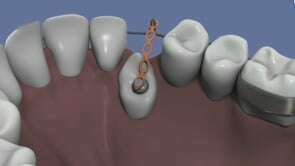

Les gouttières invisibles...

Nos conseils